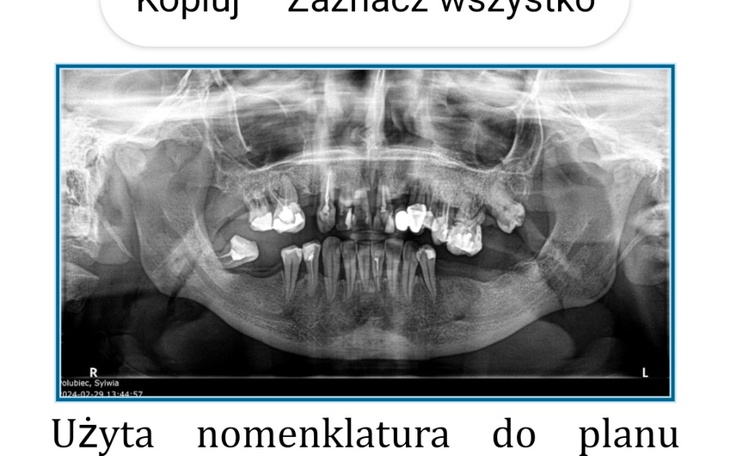

Witajcie kochani bardzo proszę was o pomoc w ratowaniu moich zębów. Mam 42 lata i bardzo duży problem z zębami. Zaczęła mi się ruszać górna jedynka i po wizycie u dentysty dostałam skierowanie do lekarza Periodontologa i tam dowiedziałam się że mam zanik kości w szczęce. Jedyne wyjście to jest odbudowa kości szczęki żebym nie została beż zębów. Ale niestety koszty odbudowy kości są bardzo drogie. Niestety nie stać mnie na to. Dlatego bardzo proszę was o pomoc. Każda wpłata złotówki się liczy. Nie chcę w tak młodym wieku zostać bez zębów bo nawet nie będę miała możliwość założenia protezy bo nie będzie miała na czym się trzymać 😥